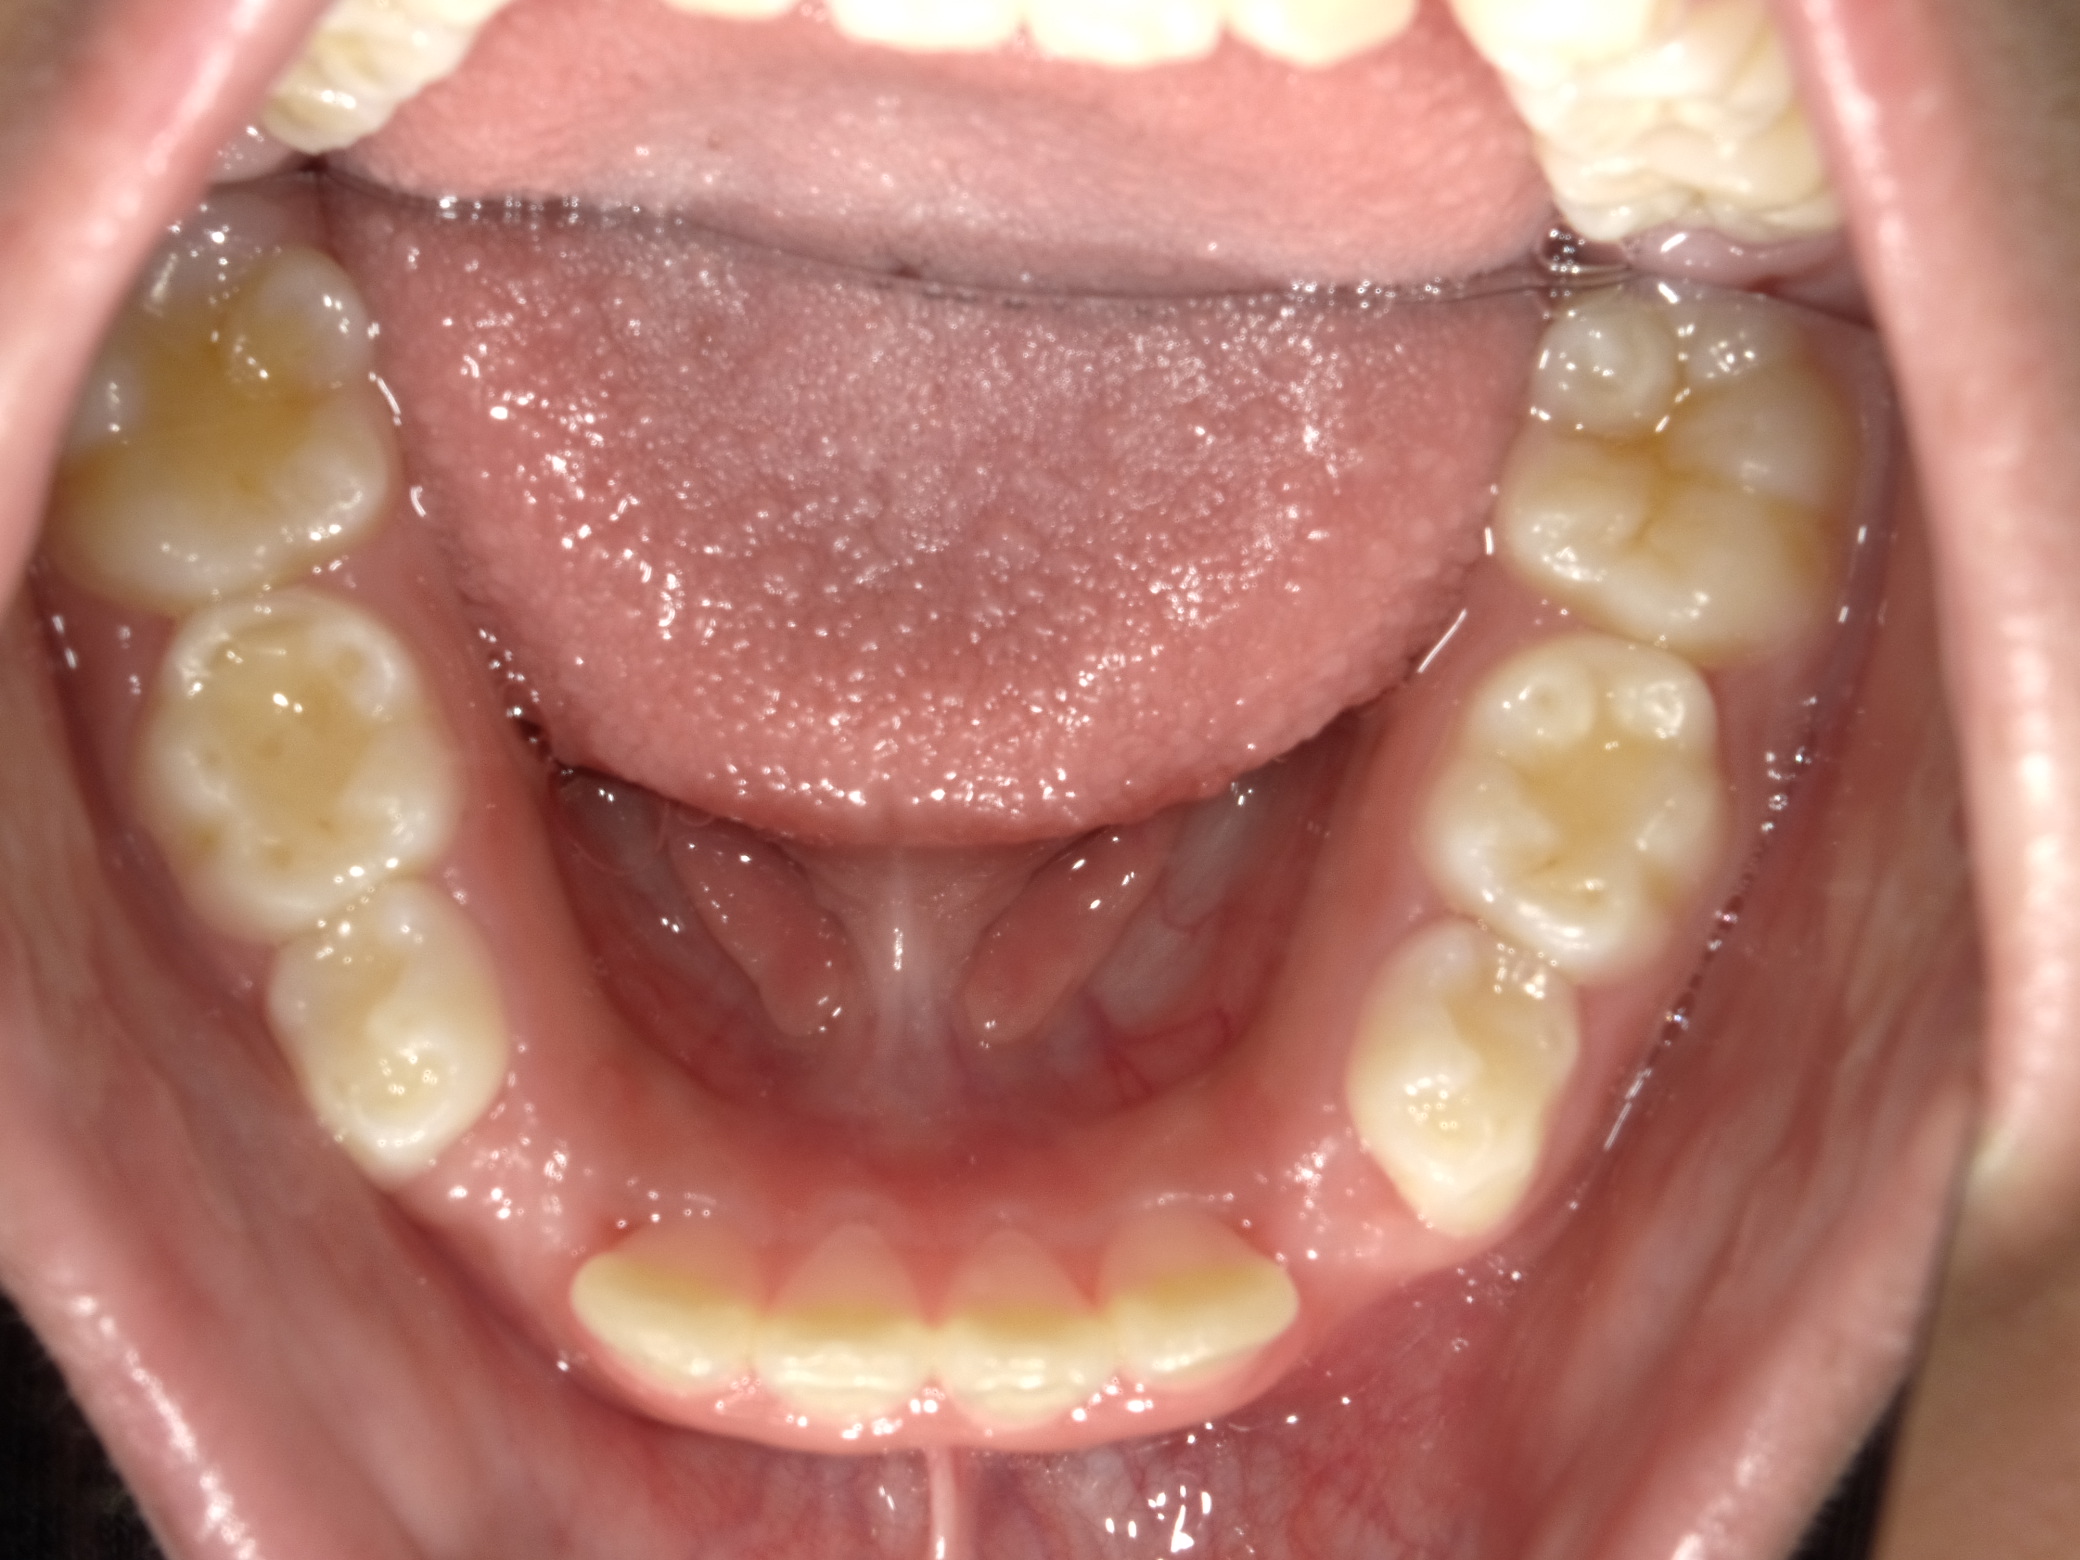

下顎

| 治療内容 | インビザライン・ファースト |

| 治療詳細 | スペース不足や交叉咬合を整えるために、歯の表面にアタッチメント(白い突起)をつけ、治療を行いました。 |

| 患者情報 | 9歳 男性 予防矯正から移行 |

| 主訴 | 永久歯は生えそろう十分なスペースがない 一部分だけかみ合わせが反対 |